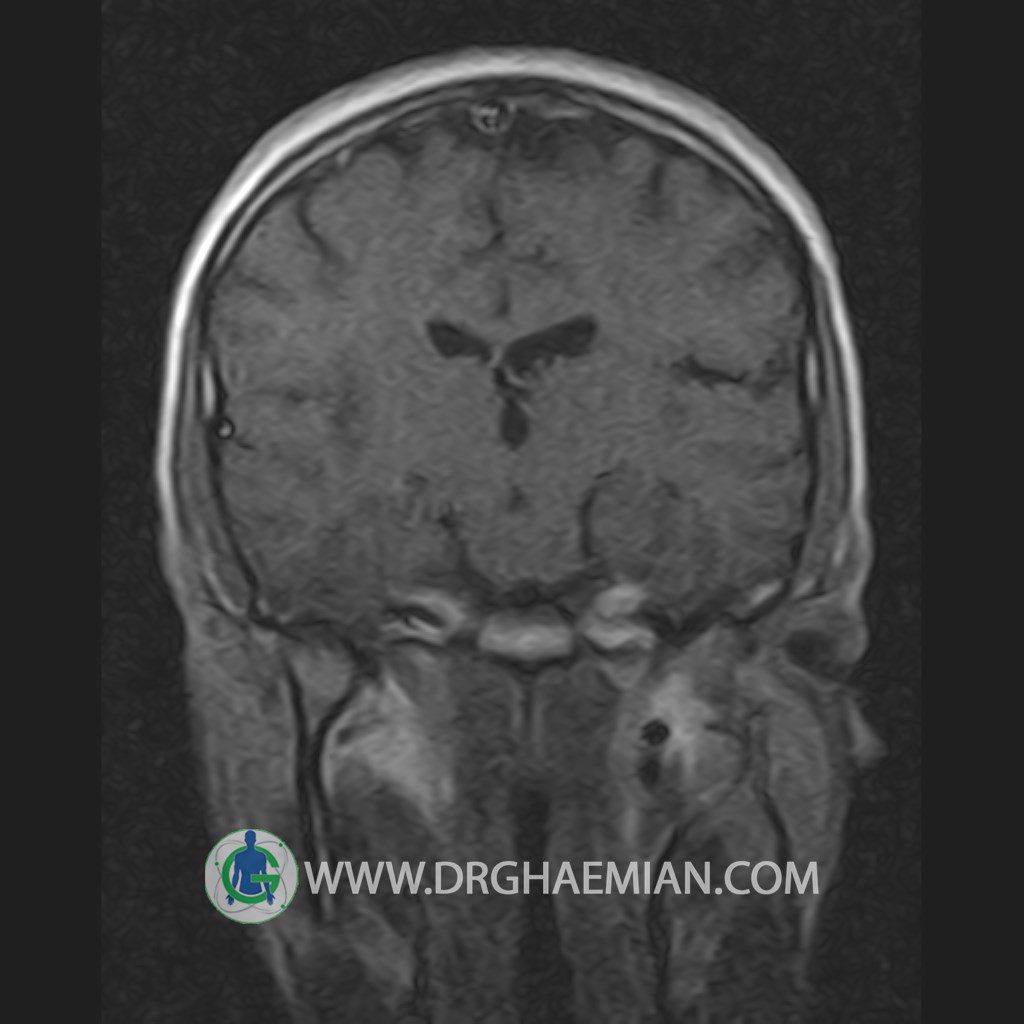

پزشکان اغلب از تصویربرداری ام آر آی برای تشخیص و درمان عارضه های پزشکی که فقط با استفاده از اشعه ایکس یا میدان مغناطیسی و امواج رادیویی قابل مشاهده است، استفاده می کنند. دستگاه ام آر آی تصاویر دقیق از ساختار های داخلی بدن ایجاد می کند. در این کیس یک میکروآدنوم در هیپوفیز بیمار مشاهده می شود.

HYPOPHYSIS MRI

(with and without contrast)

Technique: Axial , coronal T1 , Axial , coronal , sagittal T2 , Axial, coronal T1 post Gd & 64 dynamic thin coronal slices.

REPORT :

– Small hypoenhancing mass lesion ( 3 x 4 mm ) in posterior of pituitary stalk suggestive for micro adenoma

– Mucosal thickening in ethmoid & maxillary sinuses

is seen